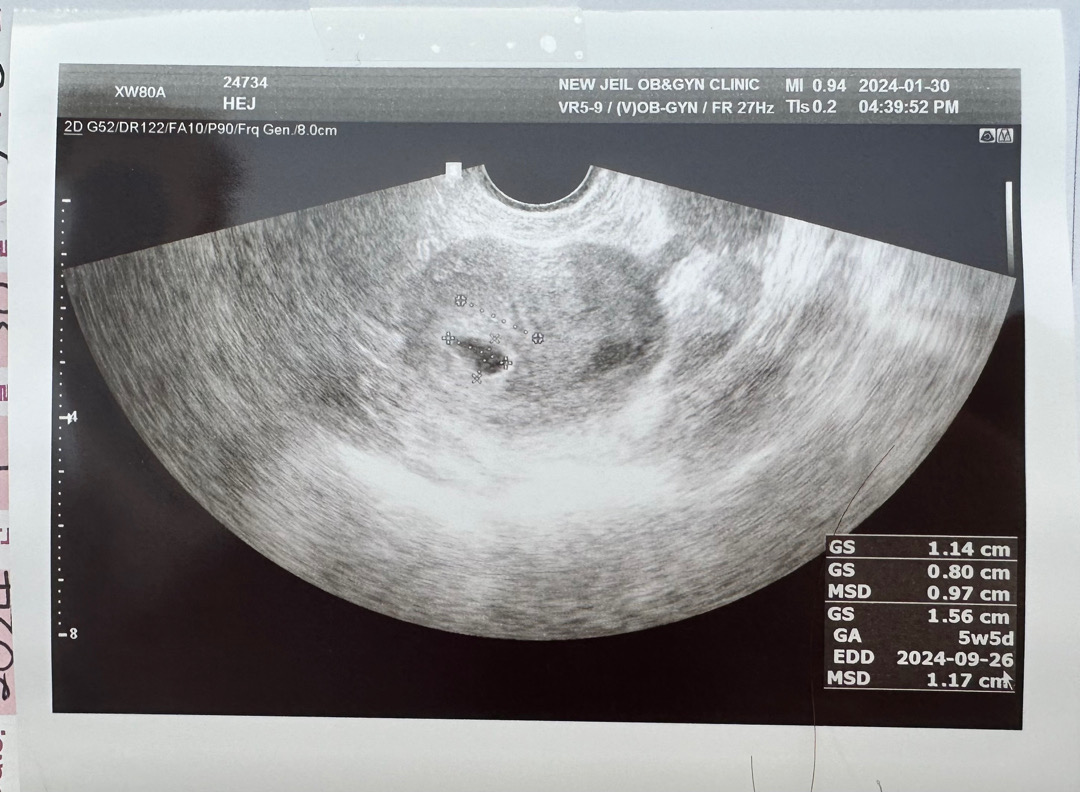

28일에 임테기해봤는데 두줄 나와서 어제 남편한테 말해주고, 오늘 병원가서 아가집도 보고왔네요ㅎ 임신 3주차인줄 알았는데 주차계산해보구 확인해보니 5주차였네용..ㅎ 5주차 예비맘인데, 혹시라도 제가 실수할까 걱정이 많네요..ㅠㅠ

저도 첨엔3주차로 들엇는데 뭔가 이상하기도해서 다시 병원에 물어보니 5주차라고하네요!

아! 혹시나해서..병원에 물어보니.. 5주차라고하네요!3주차가 아니엇더라구요!